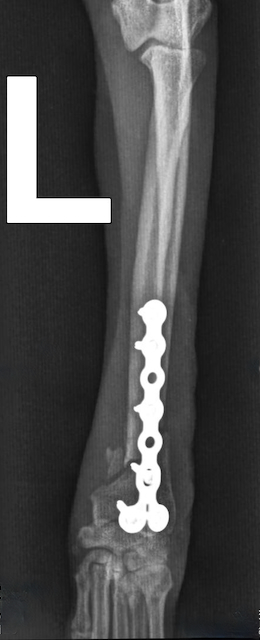

Bei der Nachoperation setzte Chirurg Maximilian Herion statt der gebrochenen Platte eine identische neue ein. Die Verwendung eines dickeren Implantats verbot sich wegen Hugos filigranem Knochen. Auch diesmal verlief die OP erfolgreich. So dass wir Hugo samt Herrchen mit guten Wünschen und einer erneuten Ermahnung, den Hund in einem Kinderlaufstall oder Käfig zu halten, nach Hause verabschieden konnten.